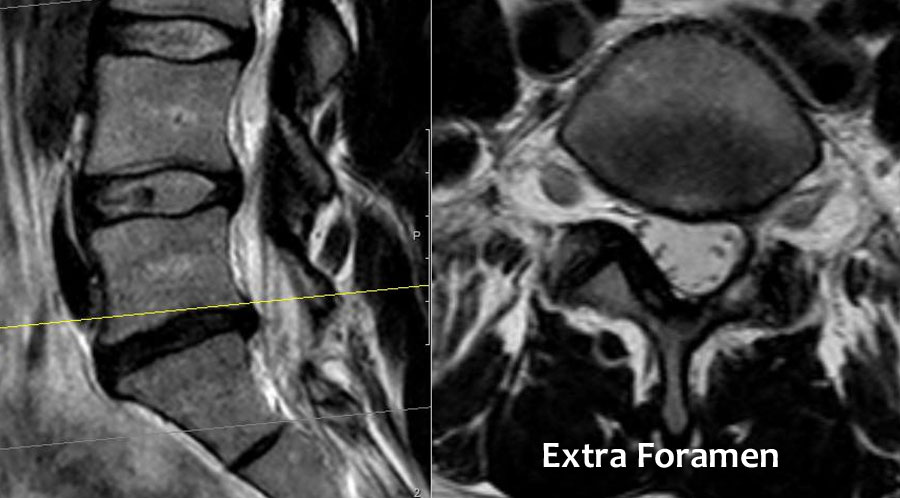

Cuộn qua các hình ảnh để quan sát đường đi của các rễ thần kinh tại mức độ đĩa đệm, ngách bên, lỗ liên hợp và ngoài lỗ liên hợp.

Tại mỗi mức độ có thể thấy các bệnh lý đặc trưng, nhưng có sự chồng lấp đáng kể.

Ví dụ, đĩa đệm có thể thoát vị và gây chèn ép thần kinh tại mức độ đĩa đệm, nhưng cũng có thể di trú xuống tầng thấp hơn và chèn ép rễ thần kinh trong ngách bên, hoặc di chuyển lên trên và gây chèn ép tại mức độ lỗ liên hợp hay ngoài lỗ liên hợp.

Hẹp lỗ liên hợp được gặp trong thoái hóa khớp mỏm khớp, trượt đốt sống và thoát vị đĩa đệm trong lỗ liên hợp – thường là đĩa đệm di trú từ tầng thấp hơn. - Ngoài lỗ liên hợp.

Đây là vùng nằm bên ngoài lỗ liên hợp.

Chèn ép thần kinh tại vùng này không phổ biến, nhưng đôi khi do thoát vị đĩa đệm sang bên gây ra.